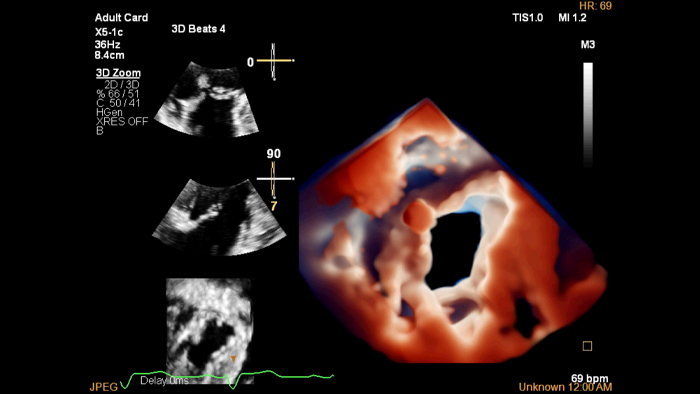

The EPIQ CVx is a dedicated cardiac ultrasound solution which brings significant advancements in functionality. This helps you deliver better care through higher processing power, exceptional imaging with more clarity & sharpness, improved exam efficiencies, complemented by the proven, robust quantification capabilities of Ultrasound Workspace.